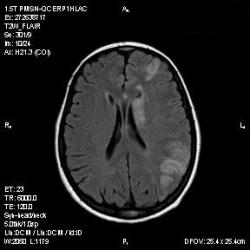

Из анамнеза - Женщина 45 лет. За год похудела на 15 кг (со слов матери), в последние месяцы случались эпизоды потери сознания. Онкозаболеваний и прочая в анамнезе нет. Сознание спутанное, из особенностей в анализах только подъем амилазы крови.

К сожалению, не владею методом КТ, но учитывая наличие неравномерного уплотнения в мозговых структурах с элементами очаговых "вкраплений", единственное, что приходит на ум - это рассеяный склероз. Хотелось бы уточнить, что беспокоило пациентку в течение последнего года кроме потери веса и эпизодов потери сознания? Была ли какая-либо очаговая неврологическая симптоматика? Отмечались ли какие-либо расстройства в двигательной или чувствительной сфере и т.д.? С уважением Helenmar.

И это точно не РС, т.к. характер очагов другой, ни один из них не копит контраст, нет субтенториальных очагов (извиняюсь, я этого в сообщении не указал), нет клиники.

"Раскрою" карты. Мы подумали о синдроме MELAS (mitochondrial encephalomyopathy, lactic acidosis and stroke) - дословно, митохондриальная энцефаломиелопатия, лактоацидоз и инсульт. В качестве дифференциальной диагностики можно было бы предположить вирусный энцефалит, но опять-таки, расположение очагов смущает - только с одной стороны и в абсолютно различных структурах.

В данном случае мы видим импульную последовательность FLAIR - режим с подавлением сигнала от воды, поэтому ликвор гипоинтенсивен, а также (вторая серия) - изображения, взвешенные по T1 после введения контрастного препарата. На T1 жидкость (ликвор) также представляется гипоинтенсивной. Зато на этих сериях гиперинтенсивны сосуды, т.к. контрастное вещество циркулирует в кровяном русле.

Изменения носят сосудистый характер. Процесс достаточно острый, имеется объемное воздействие, борозды левой гемисферы компремированы. По поводу MELAS синдрома очень сомневаюсь, почему поражена только левая гемисфера? Надо делать МР-ангиографию, смотреть нет ли стеноза

MELAS синдром - дебютирует с детских лет, характерен целый комплекс неврологических проявлений, заболевание генетическое, поражение системное, хотя есть множество вариантов митохондриального поражения, все же сомнительно. Хотелось бы акцентировать внимание, что гиперинтенсивные очаги есть в мозолистом теле, поражены выражено перивентрикулярные отделы, U -пути, белое вещество, поэтому так категорично демиелинизацию не вычеркивала бы из дифряда ( хотя тоже нетипично односторонее поражение). Думаю, для объективных выводов все же мало общей информации о пациентке, были ли клинические эпизоды раньше, чем объяснить такую потерю веса (возможно есть проявление паранеопластического синдрома?). Ну и МРТ-контроль в динамике, ангиография.

Да, неоднозначный случай. Точно не РС и не ОНМК. Я бы написала асимметричную лейкоэнцефалопатию неясного генеза. Можно было бы думать о лимфоме (полифокальное поражение, да еще мозолистое тело вроде бы задействовано (эх, сагиттальчики бы)). Но! Учитывая отсутствие накопления КВ.... Ну и надо исключать интоксикацию, всяческие аутоиммунные процессы (в т.ч. и васкулиты), сахарный диабет, ну и естественно наследственную патологию обменных процессов. УУУх! Вот.......

Имхо ишемический онмк в бассейне сма. Особенно показательны 5-й и 6-й файлы, отграничение как раз на границе бассейнов средней и перикаллёзной. Плюс одностороннее поражение.